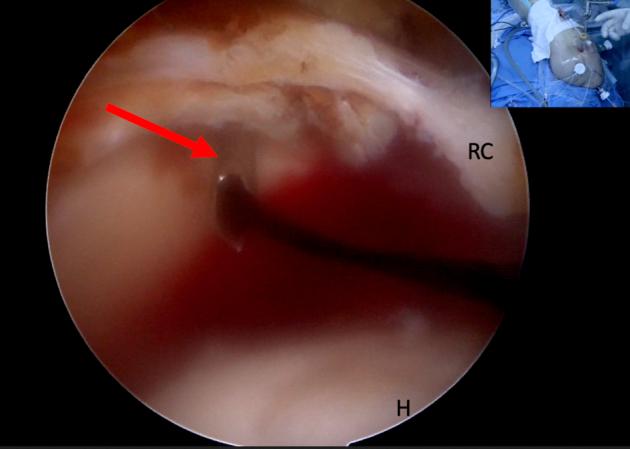

使用阔筋膜自体移植片重建不可修复性肩袖撕裂

Rotator Cuff Reconstruction Using Fascia Lata Patch Autograft for the Nonrepairable Rotator Cuff Tear.

A large to massive rotator cuff tear is a common issue that lacks reliable options to return a patient's range of motion and function when conservative treatment has failed. With up to 96% of massive rotator cuff repairs failing within the first 6 months of repair, surgeons have been searching for a reliable treatment option for this difficult subset of patients. Surgical options for massive, retracted rotator cuff tears include re-establishing the counterforce coupling of the rotator cuff with techniques such as a partial repair or superior capsular reconstruction, preventing superior humeral migration as seen with balloon spacer implantation, and eliminating pain generators with techniques such as biceps tenotomy; however, these do not reconstitute dynamic cuff control. More recently, an acellular dermal allograft, as seen in superior capsular reconstruction, has been used to reconstruct the remaining rotator cuff. We describe a technique using a fascia lata autograft to reconstruct the rotator cuff in the setting of a massive cuff tear. This is of particular importance in centers that lack the funding or institutional approval to use acellular dermal allografts that have been popularized to date.

摘要